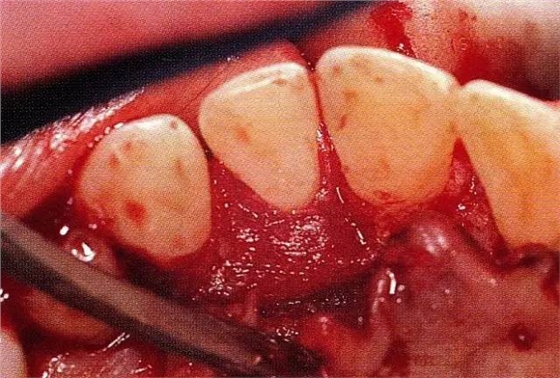

▲圖7-4術(shù)后1年2個(gè)月再翻開看的情況。與圖7-1的骨缺損狀態(tài)相比可知形成了臨床性骨再生。

▲圖7-5此狀態(tài)下,左下5的遠(yuǎn)中存在牙槽骨不平整,因此進(jìn)行了骨修整。同時(shí),將骨膜留存,進(jìn)行了齦瓣根尖側(cè)移動(dòng)術(shù),去除了牙周袋。